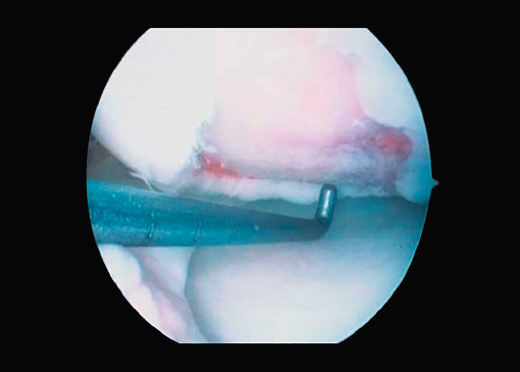

First surgery involves arthroscopy of the damaged joint. It assesses the chondral lesion to be treated and confirms whether it is amenable to the chondrocyte implantation technique (Figures 1 and 2). Other procedures are also carried out if needed, such as for example reconstruction of the anterior cruciate ligament, partial meniscectomies, meniscus implantation, patellar realignments, osteotomies, etc. Lastly, the cartilage sample is taken from a non-weight bearing zone (intercondylar zone or internal femoral condyle at its upper margin). The sample is extracted with biopsy forceps or, alternatively, using discectomy forceps. Between 3-4 rice grain-sized fragments of healthy cartilage are harvested (Figure 3). The biopsy material is placed in a sterile receptacle containing a culture medium (DMEN) (Figure 4). The material is kept at room temperature and is shipped to the laboratory as quickly as possible. A form should be completed (Figure 5), stating the joint, the location of the lesion and the size of the defect. Once in the laboratory, the sample is processed and cultured. After 4-6 weeks (depending on the case), the culture is ready for implantation.

2. The damaged cartilage is cleaned using curettes, with debridement of the defect, and the lesion is left with healthy and exposed subchondral bone (Figure 7).